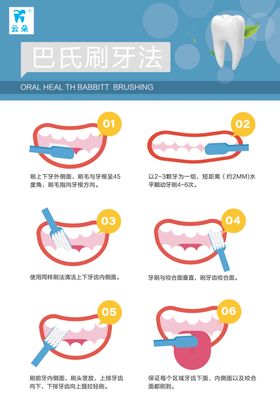

巴氏刷牙科口腔